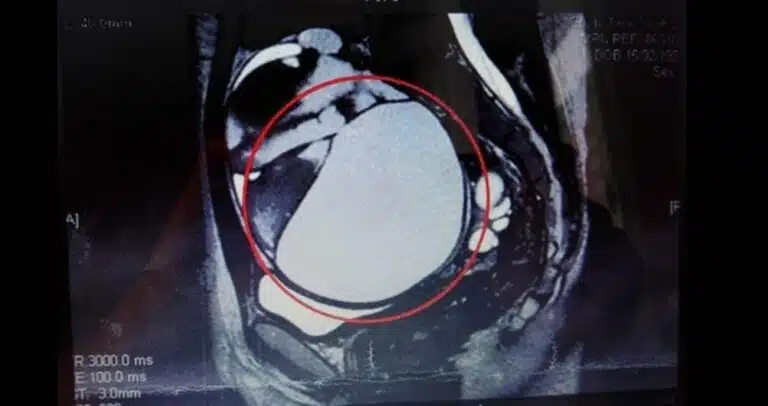

Dzięki pomocy lekarzy po wielu latach cierpień 57-letnia Chinka nareszcie może oddychać swobodnie. Kobieta przez większość swojego życia zmagała się…